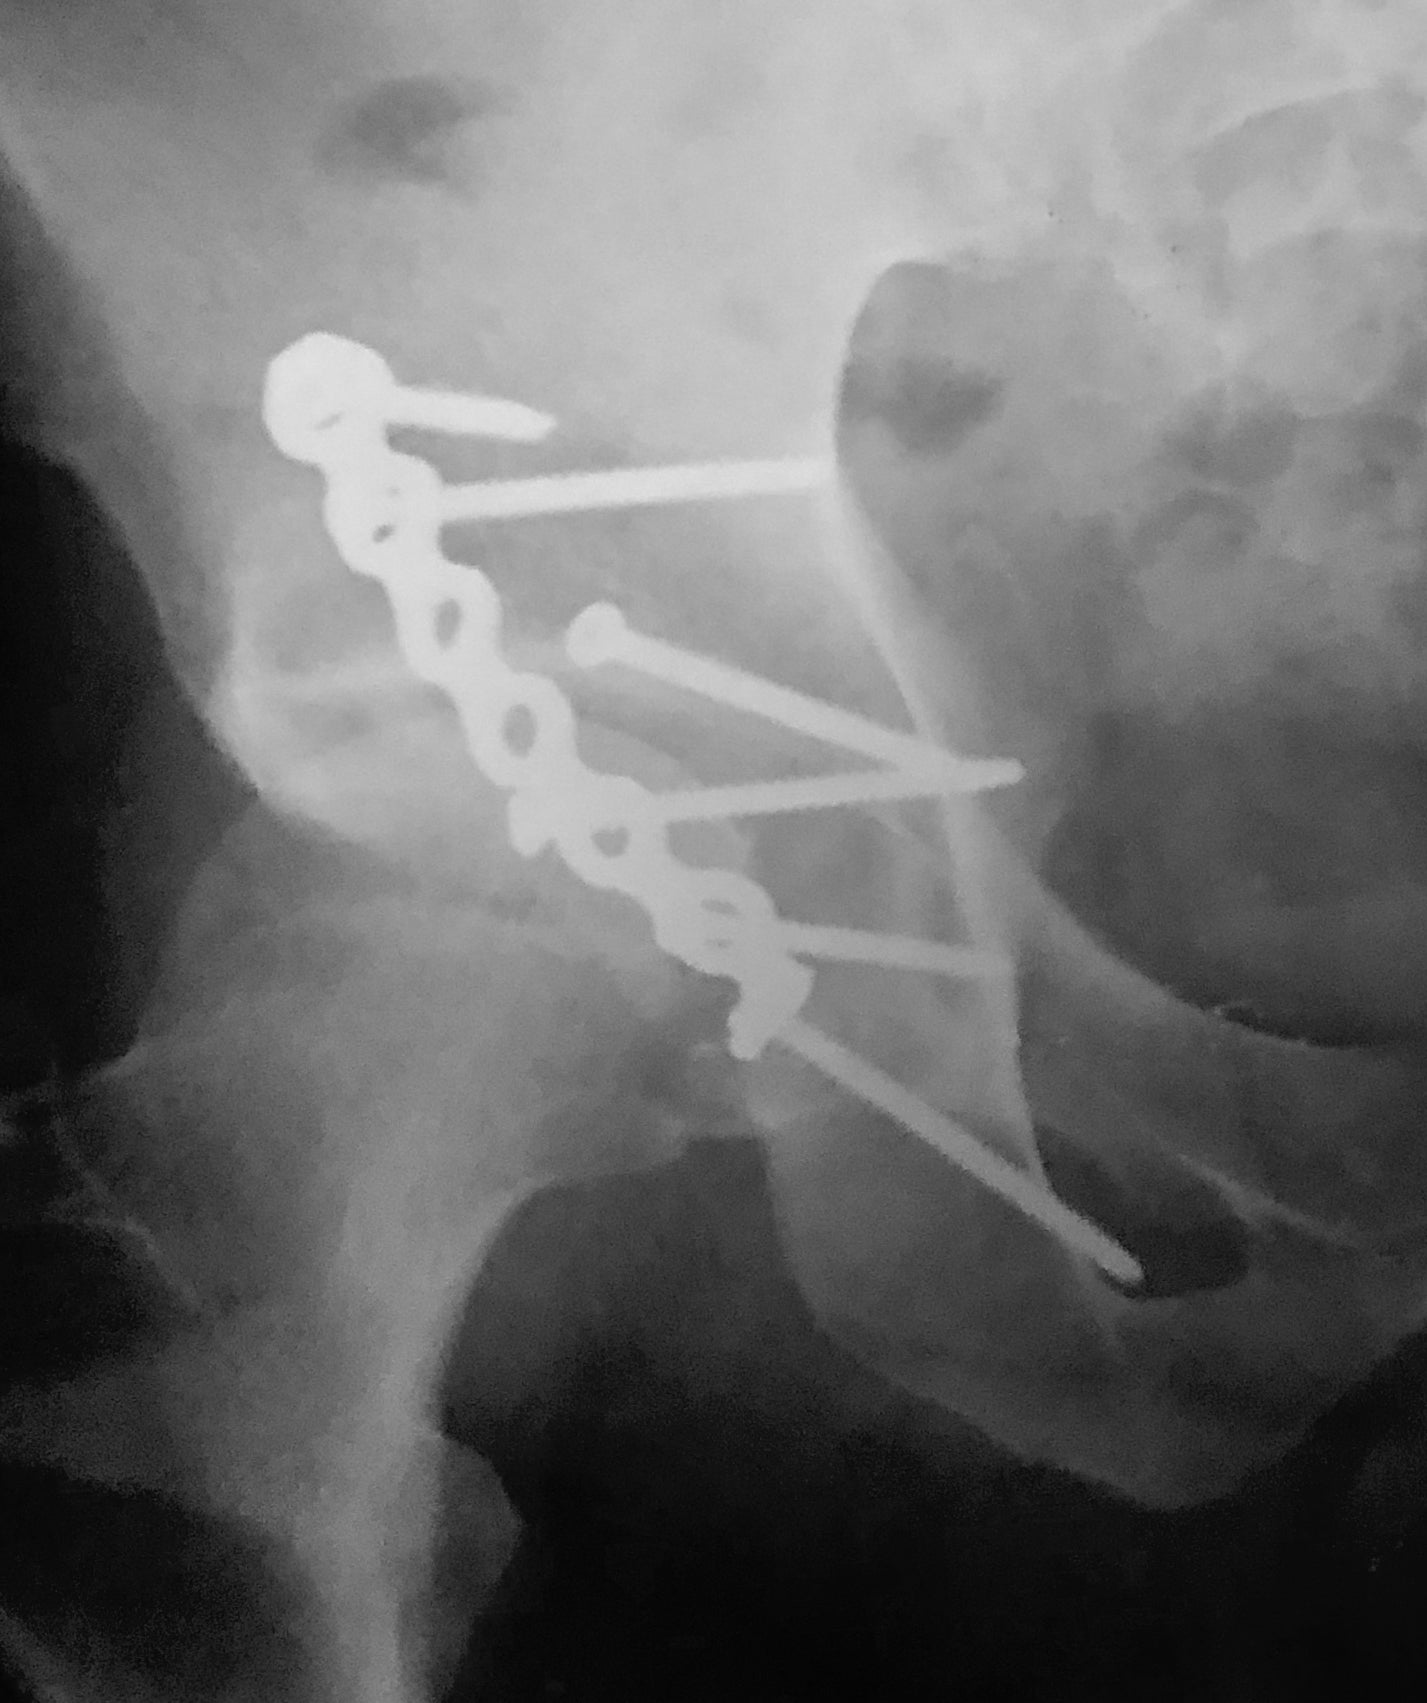

写真でご覧のとおり、見るからに元気ではあるのですが、実はぼくの身体は大動脈が人工血管になり、右足の大腿骨と膝は数本のボルトで繋がれています。

(以下、レントゲンや縫合後のお見苦しい画像がありますがご容赦ください)。